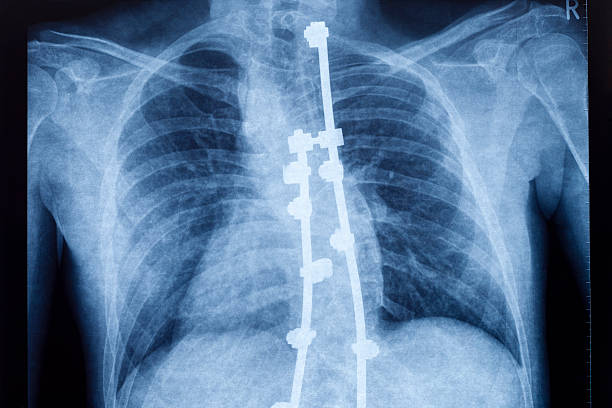

척추전방전위증은 머리와 목의 자세가 정상적인 위치에서 벗어나고, 머리가 앞으로 기울어지는 상태를 의미합니다.

이 자세 문제는 허리 통증과 더불어 다양한 증상을 유발할 수 있으며, 많은 사람들이 이에 대한 운동을 찾고 있습니다.